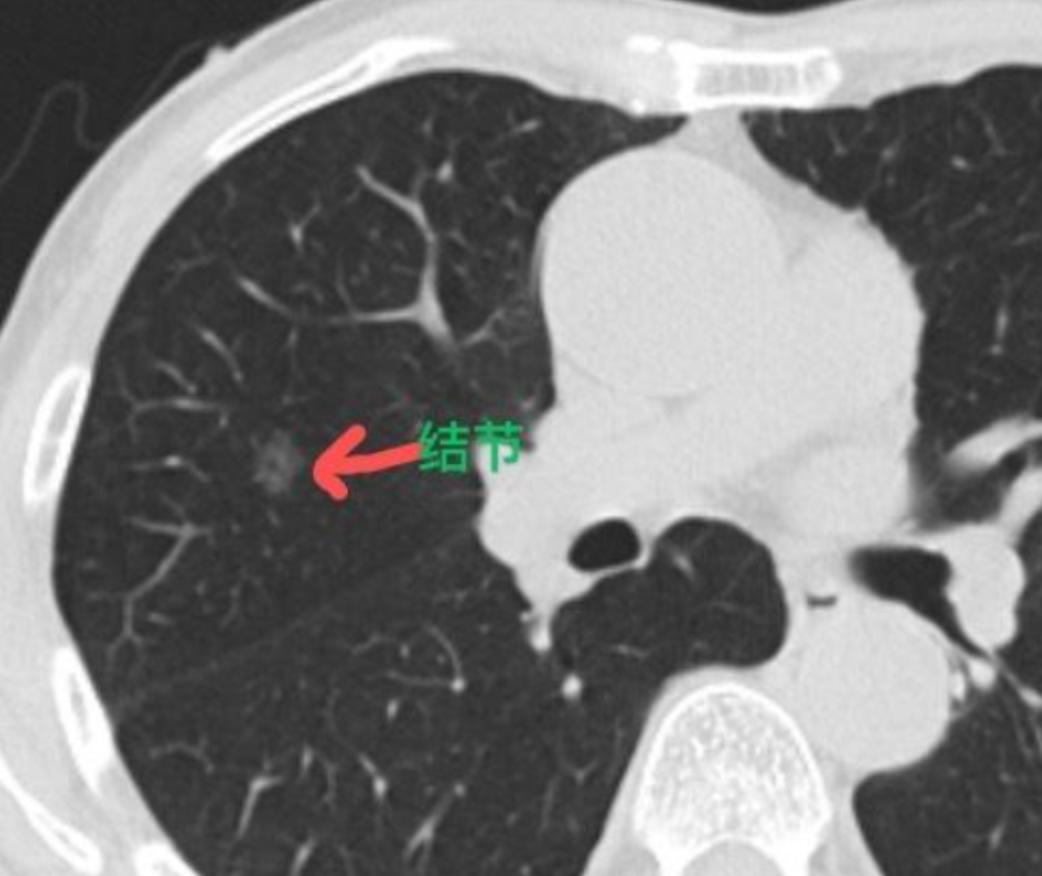

这位男性患者35岁,在体检中发现右肺有一个磨玻璃结节,已经随访快一年了,大小和形态一直没变化。从影像上看,我们判断它大概率是早期的原位癌或者微浸润癌。 他来门诊找我时,整个人状态很焦虑。他说自从查出这个结节,饭也吃不好、觉也睡不踏实,心理压力特别大。 细问才知道,原来他家里有亲人得过肺癌,查出来时已经是晚期,所以他对“观察等待”特别抗拒,一直希望我能尽快给他安排手术。 我跟他详细解释过,像他这种磨玻璃结节,密度低、个头小,目前定期随访是非常安全的,不会扩散也不会转移。哪怕未来真有变化,再手术也完全来得及,效果一样好。 但他态度很坚决,就是不想再等了。考虑到结节的性质比较明确,我们给他做了三维重建,仔细规划手术方案,希望能尽量帮他保留正常的肺组织。 这个结节的位置在肺的亚段——如果把肺比作一棵树,亚段就像是主干分出来的小分支。最后我们为他做了亚段切除,只切除了很小一部分肺组织,结节完整拿掉了。 术后病理证实是微浸润腺癌,因为发现得早、处理得及时,术后也不需要放化疗,达到了治愈的效果。 作为医生,我一直主张“没有变化就不急于手术”。但这次我也意识到,当一颗结节已经严重影响到患者的正常生活和情绪,而医学上也具备安全切除的条件时,尊重患者的意愿,用最小的代价解决问题,或许也是一种负责任的选择。 毕竟,能让他彻底安心,回归正常生活,同样是治疗的重要目标。[玫瑰][作揖]胸外科乔贵宾医生MCN双量进阶计划 [心]附:线下免费义诊!11月21日(周五上午),在南方医科大学珠江医院 门诊大厅